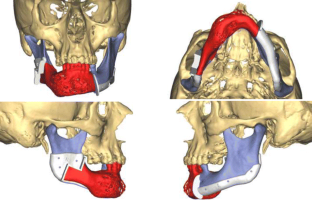

At present, mandibular reconstruction with a fibular free flap is the gold standard for functional and esthetic rehabilitation after oncological surgery. The purpose of this study was to describe the computer-assisted mandibular reconstruction procedure adopting the customized solution Synthes ProPlan CMF. The study reports five consecutive patients with benign or malignant disease requiring mandibular reconstruction using a microvascular fibular free flap, pre-operative virtual planning, construction of cutting guides and customized laser pre-bent titanium plates. The surgical technique is discussed in a step-by-step fashion. The average post-operative hospital stay was 18 ± 3 days. Ischemia time was recorded in all five cases, with an average of 75 ± 8 min. No problems were encountered in any surgical step and there were no major complications. Excellent precision of cutting guides and a good fit of pre-bent plates were found on both the mandible and fibula. There was excellent precision in bone to bone contact and position between mandible and fibula graft. Measurement data from the pre-operative and post-operative CT scans were compared. The average difference (Δ) between programed segment lengths and CT control segment lengths was 0.098 ± 0.077 cm. Microsurgical mandibular reconstruction using a virtual surgical planning yields significantly shorter ischemia times and allows more precise osteotomies. The technology is becoming increasingly recognized for its ability to optimize surgical outcomes and minimize operating time. Considering that the extent of resection can be wider than predicted, this results in safer modeling of the fibula only after frozen sections have demonstrated the radicality of resection.